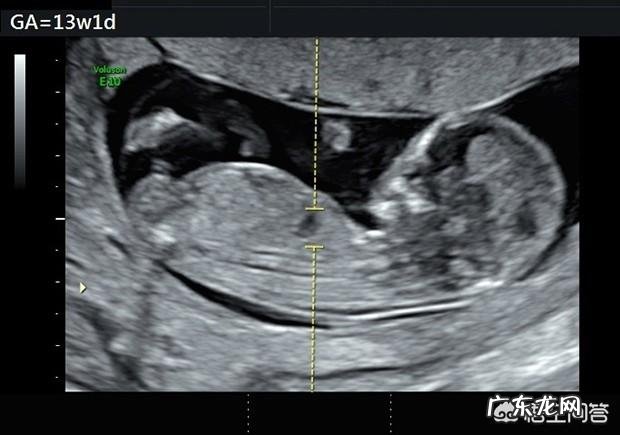

孕13周胎儿的大小是7~8cm,股骨长约1.17~1.48cm,双顶径约2.52~2.77cm,体重约20~25g,身体和手臂的比例接近出生时的状态 。子宫的大小如甜瓜,从B超中能清楚看到胎儿脸部的轮廓,器官基本成形 。

NT检查黄金时间是孕11-14周,还没照NT检查透明层的孕妈可要抓紧时间了 。